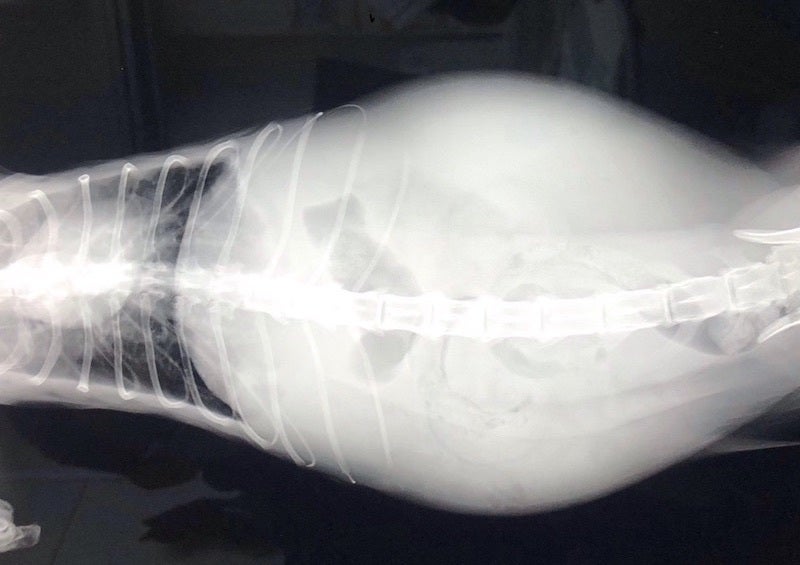

FIPという診断を受けた時に、あらゆる手段を使いこの病気について調べました。動物病院の先生やネットで調べた結果、外猫・野良猫のほとんどが持っているコロナウイルスが突然体内で変異し、FIPウイルスになるということが分かりました。FIPウイルスは一度発症してしまうと元に戻ることはありません。原因はストレスのことが多いと言われており、ずら丸にストレスを与えてしまっていたと日々嘆くばかりです。現在の症状としては腹水・胸水の貯留、食欲減退、便秘、黄疸、脱水症状です。動物病院への通院で脱水症状については収まりを見せていますが、その他は改善の兆しが見えてきません。

腹部レントゲン画像

腹部エコー画像